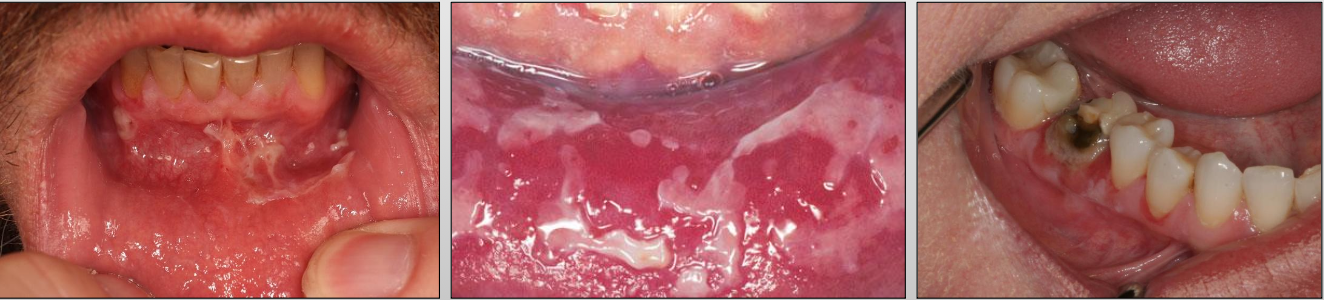

A severe, progressive autoimmune disease that affects both the skin and mucous membranes

What is Nikolsky sign in Pemphigus Vulgaris?

Gentle finger pressure with movement on clinically normal mucosa can produce acleavage in the epithelium and result in the formation of a bulla

What are Tzank cells in Pemphigus Vulgaris?

Loss of attachment between the epithelial cells results in detached cells that appear rounded, present in the area of separation

Sloughing of the epithelium Ulcers in Pemphigus Vulgaris

What is the diagnosis for Pemphigus Vulgaris?

Biopsy and Direct immunofluorescence (DIF)- INTRA-EPITHELIAL separation

What is the treatment for Pemphigus Vulgaris?

What is Mucous Membrane Pemphigoid?

A chronic autoimmune disease that affects the oral mucosa, conjunctiva, genital mucosa, and skin

Where might you find Mucous Membrane Pemphigoid?

Skin and mucosa (mouth, genital, eye)

And intraorally: gingiva (most common)

What is a unique clinical feature of Mucous Membrane Pemphigoid?

Symblepharons (fibrous scars) along the eye